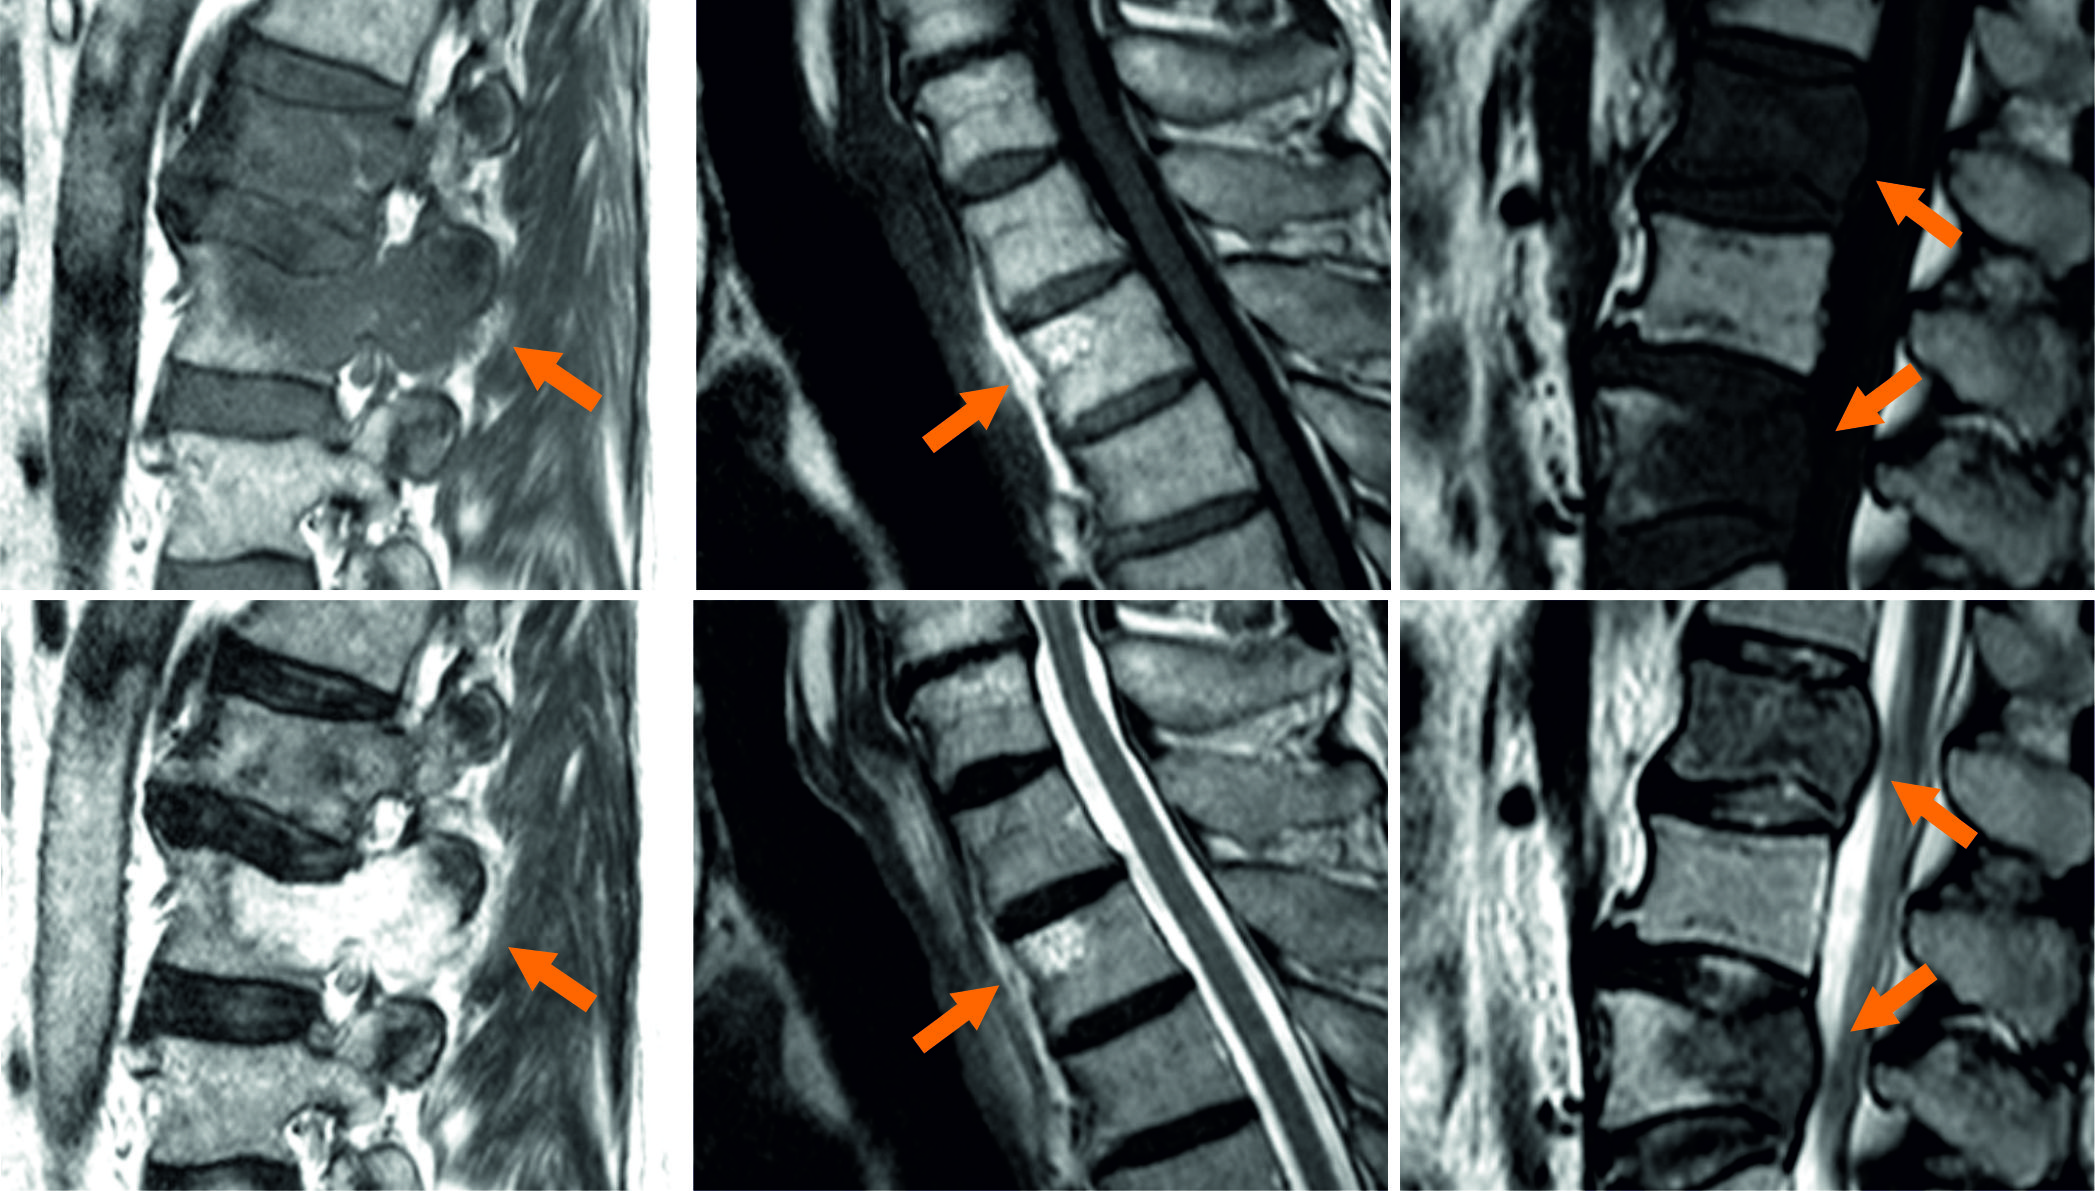

Due to the improvement of medical treatment and diagnostic procedures, life expectancy has increased steadily over the last decades. However, this lifetime gain promotes also age-related diseases like cardiovascular diseases, as well as cancer and cancer induced malicious metastases. The survival time of most malicious carcinomata has increased with improved diagnosis and treatment, hence, the probability to develop metastases raises. Beside liver and lung, bone metastases are the third most likely and thereof up to two thirds are located in the spine harrington1986metastatic ; wong1990spinal . Spinal metastases can tremendously affect the quality of life by evoking vigorous pain by fractures, bruises, spinal cord and nerve root compressions or neurologic deficits klimo2004surgical . Diagnosis and therapy planning can be done with multiple radiological imaging techniques, e.g. planar X-ray radiography, computed tomography (CT), single photon emission computed tomography (SPECT) or magnetic resonance imaging (MRI). The latter overcomes problems with radiation exposure of the aforementioned imaging techniques and has enhanced soft tissue contrast, which promotes early lesion detection and advanced diagnostic performance in terms of osseous lesions. Futhermore, spatial relationships of the metastazised vertebrae and surrounding tissues like the spinal cord or inter-vertebral discs are better visualized in MR than in CT or SPECT imaging.  Dependending on their origin, there are two common types of bone metastases: lytic lesions, which lead to increased osseous tissue disruption due to further osteoclastic activity and sclerotic lesions, leading to increased osteoblastic activity and therefore, bone tissue production. The specific type tremendously affects the appearance of the metastases in the respective MR imaging sequences, ranging from hypo- to hyperintense image signals compared to non-pathologic vertebral bone structures (see Fig. 1), making this a highly challenging and ambitious task.

Refer to caption

Figure 1: Examples of the shape and appearance variablility of different lesion types (orange arrows) in T1subscript𝑇1T_{1}-weighted (upper row) and within T2subscript𝑇2T_{2}-weighted MRI sequences (bottom row). Depicted is a epidural metastasis with an osteolytic vertebral body lesion (left column). The sagittal T1subscript𝑇1T_{1}-weighted MR image shows hypointensity with a paraspinal mass, while the T2subscript𝑇2T_{2}-weigthed image displays the lesion hyperintensely. The mid column displays hyperintensitiy in all acquired MR images, which is typical for benign hemangioma. Sclerotic metastases are displayed in the right column, showing characteristic hypointense signals compared to bone marrow in both MR images.